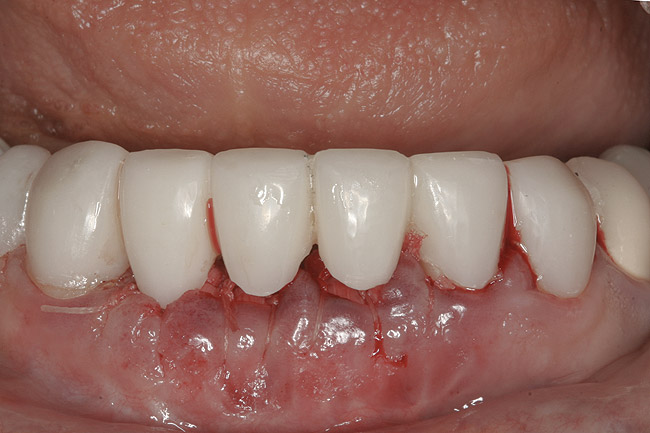

Figure 1  Initial presentation with yellow, poorly color-matched restored mandibular anterior teeth.

Figure 1

The final treatment plan called for replacement of teeth Nos. 24 through 26 with implants, and four adjacent porcelain crowns. The restorative dentist prepared these four teeth for full coverage and decoronated Nos. 24 and 25, then, with patient input, selected a shade (Figure 3) and fabricated a bis-acryl temporary bridge from Nos. 22 to 28. After extracting teeth Nos. 24 and 25, the periodontist performed socket preservation in addition to horizontal ridge augmentation in site No. 26 with FDBA and a resorbable porcine collagen membrane. The flaps were approximated with 4-0 polyglactin 910 (Figure 4). Figure 5 shows the 7-unit bis-acryl temporary bridge.

After the zirconia abutments were torqued to 20 Ncm, cotton and composite were used to cover the screw access openings. Figure 7 and Figure 8 show the finished feldspathic porcelain crowns on implants in sites Nos. 24 through 26, and on teeth Nos. 22, 23, 27, and 28; all crowns were cemented with dual-cure resin cement. Good remodeling of gingival architecture is also apparent in Figure 7. As predicted, the free gingival margin (FGM) on No. 23 is approximately 2 mm coronal to those of the adjacent implant crowns on Nos. 24 through 26 (Figure 7); as per the patient’s initial statement, this discrepancy was not an esthetic concern to her. Figure 9 shows the final post-restoration periapical view.

This patient faced a unique situation, perhaps not previously reported: retaining a healthy mandibular lateral incisor knowing this would create an esthetic compromise. Indeed, while the discrepancy in gingival-margin height is noticeable in retracted view (Figure 7), it does not show in full smile (Figure 8).